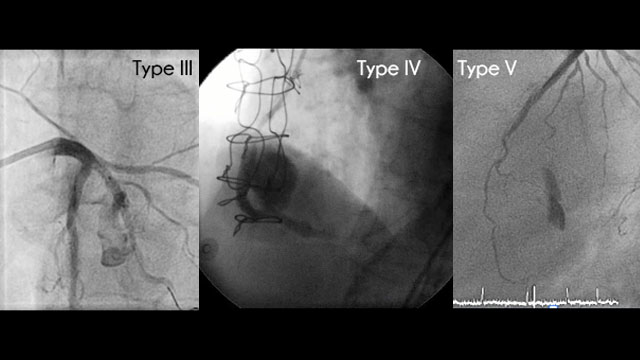

Coronary perforation

Perforations can be life threating and need to be managed correctly. Discover this section presented by O. Muller, P. Calvert, M. Haude, E. Eeckhout and A. Lerman.

Consult the complications section on Coronary perforations or visit the latest resource which explains how to manage embolised device complications like a Coronary implant loss, in particular Coronary stent dislodgement, lost scaffold, guidewire loss and balloon fracture.